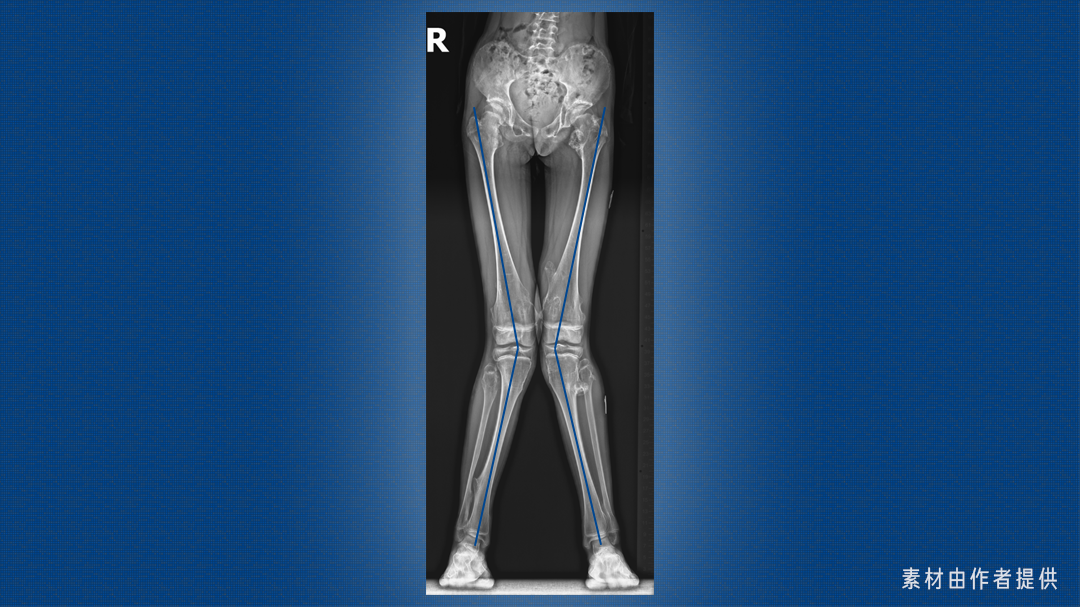

这是一双 X 型腿,医学上称为「膝外翻」,大腿和小腿轴线的交点偏向身体中轴线。

这个角度一般用胫股角来衡量,也就是大腿和小腿的轴线在膝关节处的夹角,其数值随年龄发生特征性变化。